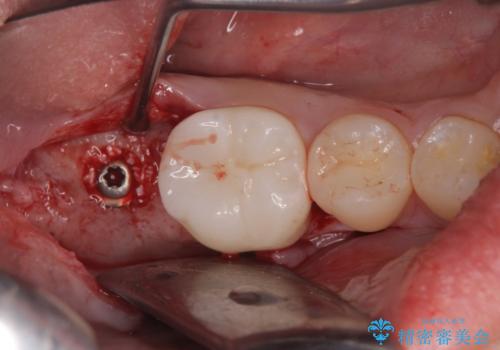

- 右下の奥歯がない状態でしばらく過ごされていた方です。

インプラント入れて噛めるようにしたいとのことだったため、治療を行います。

向かい合わせになる歯が歯茎と噛んでいるため、歯茎の厚みも調整していきます。

今回はかぶせ物の高さを確保するために、少し顎骨を削り、歯肉の厚みも薄くしました。